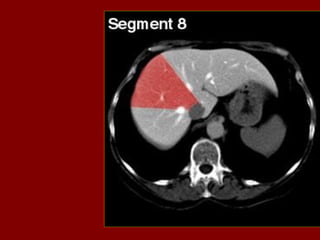

INCISÃO SOBRA AVEIA HEPÁTICA DIREITA

INCISÃO SOBRE AVEIA HEPÁTICA MÉDIA.

INCISÃO SOBRE AVEIA HEPÁTICA ESQUERDA.